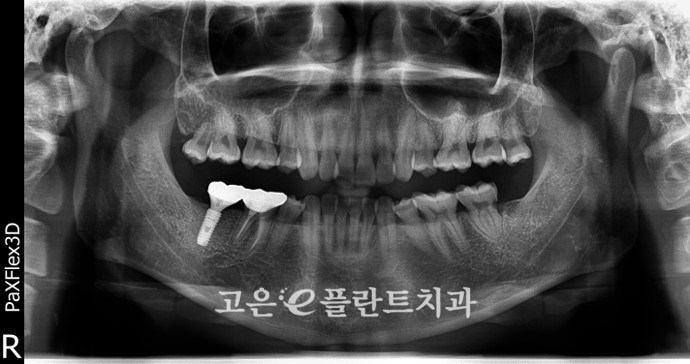

이렇게 골상태가 안좋은 경우에는

발치 즉시 임플란트가

불가능하게 됩니다.

아무리 뼈이식을 한다고 해도

고정력을 얻지 못할 가능성이 크기 때문이죠.

그렇기에 이를 빼고 나서

조금 더 기다리는 시간이 필요했습니다.

몇달 뒤 임플란트 픽스쳐를 식립하였는데요.

염증으로 인한 치조골 손상의 경우에는

다시 원래의 뼈 상태로

돌아오지 못하기 때문에

뼈이식을 통해 부족한 부분을

채워주어야 합니다.

픽스쳐가 인공뼈와 치조골과

단단히 결합되기 까지에는

충분히 기다려 주어야 합니다.

무리하게 보철을 빠르게 올리게 되면

고정력을 얻지 못하고

흔들릴 수 있기 때문입니다.